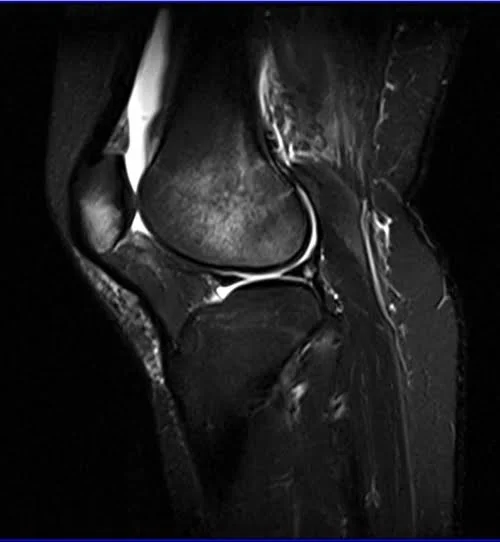

MRI knee sagittal stir 2 - MRI